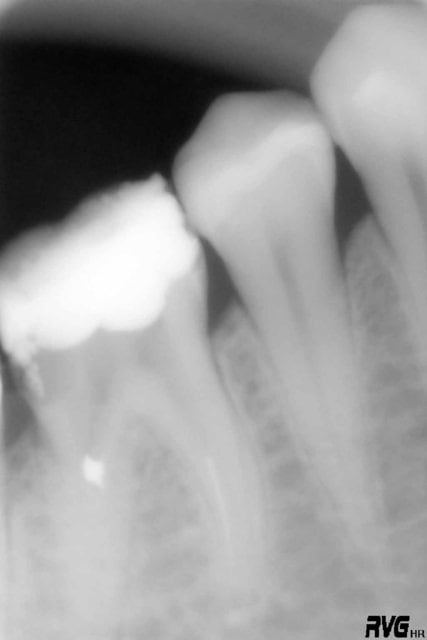

Une des premières fois que j'ai utilisé un contre-angle avec localisateur intégré.

Je me suis cru à l'abri avec le contrôle du torque sur l'instrument en temps réel.

Les diodes se sont alummées au début de la descente dans le canal et j'ai voulu continuer à avancer avec l'instrument en rotation malgré un cathétérisme manuel pas réalisé sur la totalité du canal.

Fracture , puis initiation de fausse route en essayant de passer à coté manuellement.